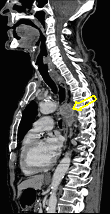

4: Miliary pattern: sarcoidosis, CT, lung window. Axial image and sagittal reformat.

A 67 year old female suffering from COPD. Bilateral rough branching interstitial widening and patchy, miliary nodules with perihilar dominance along the bronchovascular fibres and the fissures.